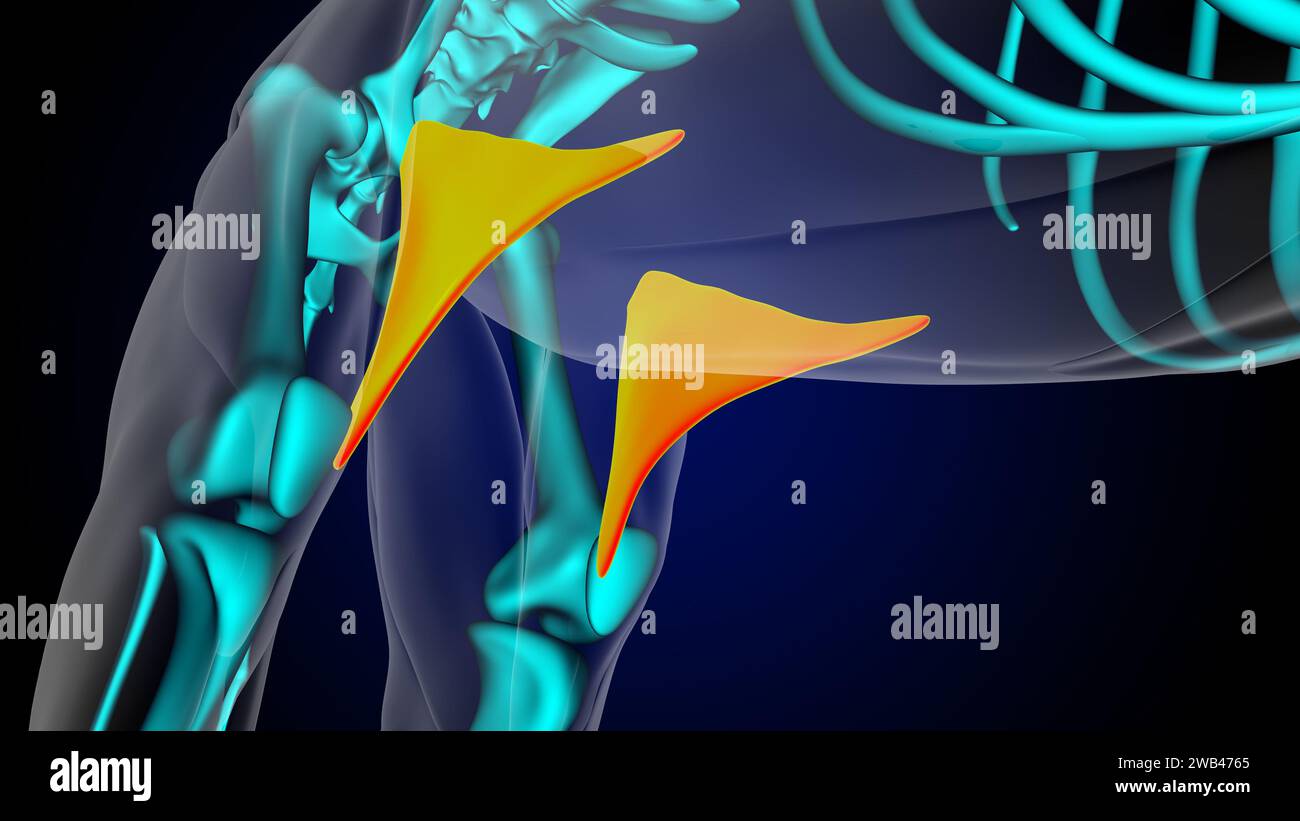

Pli à l'anatomie du muscle de lion de muscle de cuisse pour l'illustration 3D de concept médical Banque D'Imageshttps://www.alamyimages.fr/image-license-details/?v=1https://www.alamyimages.fr/pli-a-l-anatomie-du-muscle-de-lion-de-muscle-de-cuisse-pour-l-illustration-3d-de-concept-medical-image592007197.html

Pli à l'anatomie du muscle de lion de muscle de cuisse pour l'illustration 3D de concept médical Banque D'Imageshttps://www.alamyimages.fr/image-license-details/?v=1https://www.alamyimages.fr/pli-a-l-anatomie-du-muscle-de-lion-de-muscle-de-cuisse-pour-l-illustration-3d-de-concept-medical-image592007197.htmlRF2WB4765–Pli à l'anatomie du muscle de lion de muscle de cuisse pour l'illustration 3D de concept médical